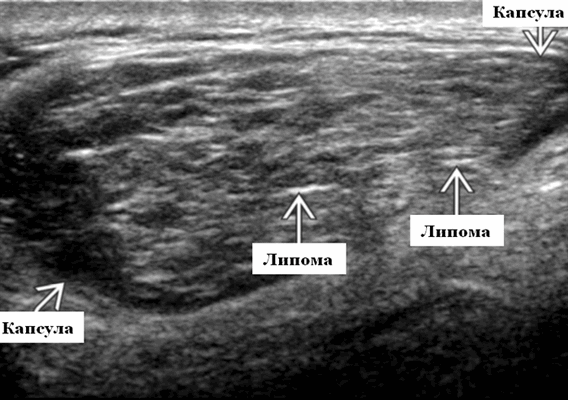

Ультразвуковая картина липомы и липосаркомы довольно сильно отличается.

Основное отличие - наличие активного кровотока в ткани липосаркомы. А практически все виды липом на УЗИ всегда имеют равномерную плотность и никогда не фиксируется кровоток.

Большинство липом, которые мы исследуем на УЗИ находятся подкожно. Они мягкие или эластичные при пальпации и относительно сжимаемы. Они возникают в любом месте на туловище или конечностях. При ультразвуковом исследовании липомы обычно одиночные, но могут быть множественными в 5-15% случаев.

УЗИ с подозрением на липому показывает яйцевидные, эллиптические или инкапсулированные подкожные массы, которые аваскулярные при допплеровском картировании и может содержать короткое яркое эхо внутренние бороздки, которые идут параллельно к коже. Большинство липом менее 10 см, но чаще их размер в 80% на УЗИ менее 5 см. В структуре варьируется яркое и темное эхо в зависимости от относительного состава жира, соединительной ткани и воды. Появление скопления нормального жира может быть трудно отличить от очаговой липомы и в данном случае тканевая гармоника может помочь определить структуру образования.